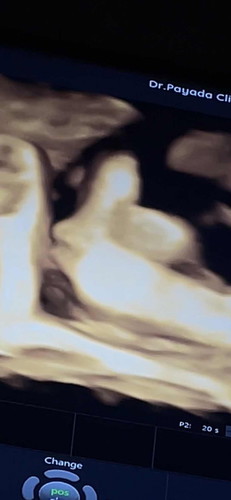

36+5 วีค กำหนดคลอด 13 ธันวาคม

ท้องแข็งทุก7นาที ปวดท้องระดับ7/10 เเต่ปากมดลูกไม่เปิด โดนป้าหมอแหย่อะไรไม่รู้โคตรจุก ออกมาได้แล้วนะ แม่ไม่ไหวแล้ว5555 #ลูกสาวคนแรก